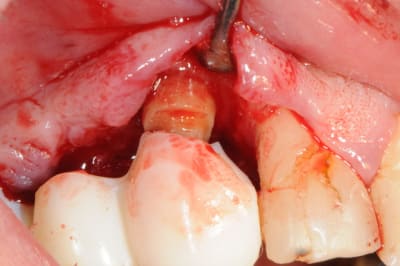

sinon, voici le protocole pour une élongation coronaire.

(c'est juste un petit cas clinique, pas La solution)

laisser au moins deux mois après la chirurgie avant d'attaquer la prothèse définitive.

oups , il manque les photos..

petite critique ; j'aurai aussi pu déplacer apicalement la gencive attachée...